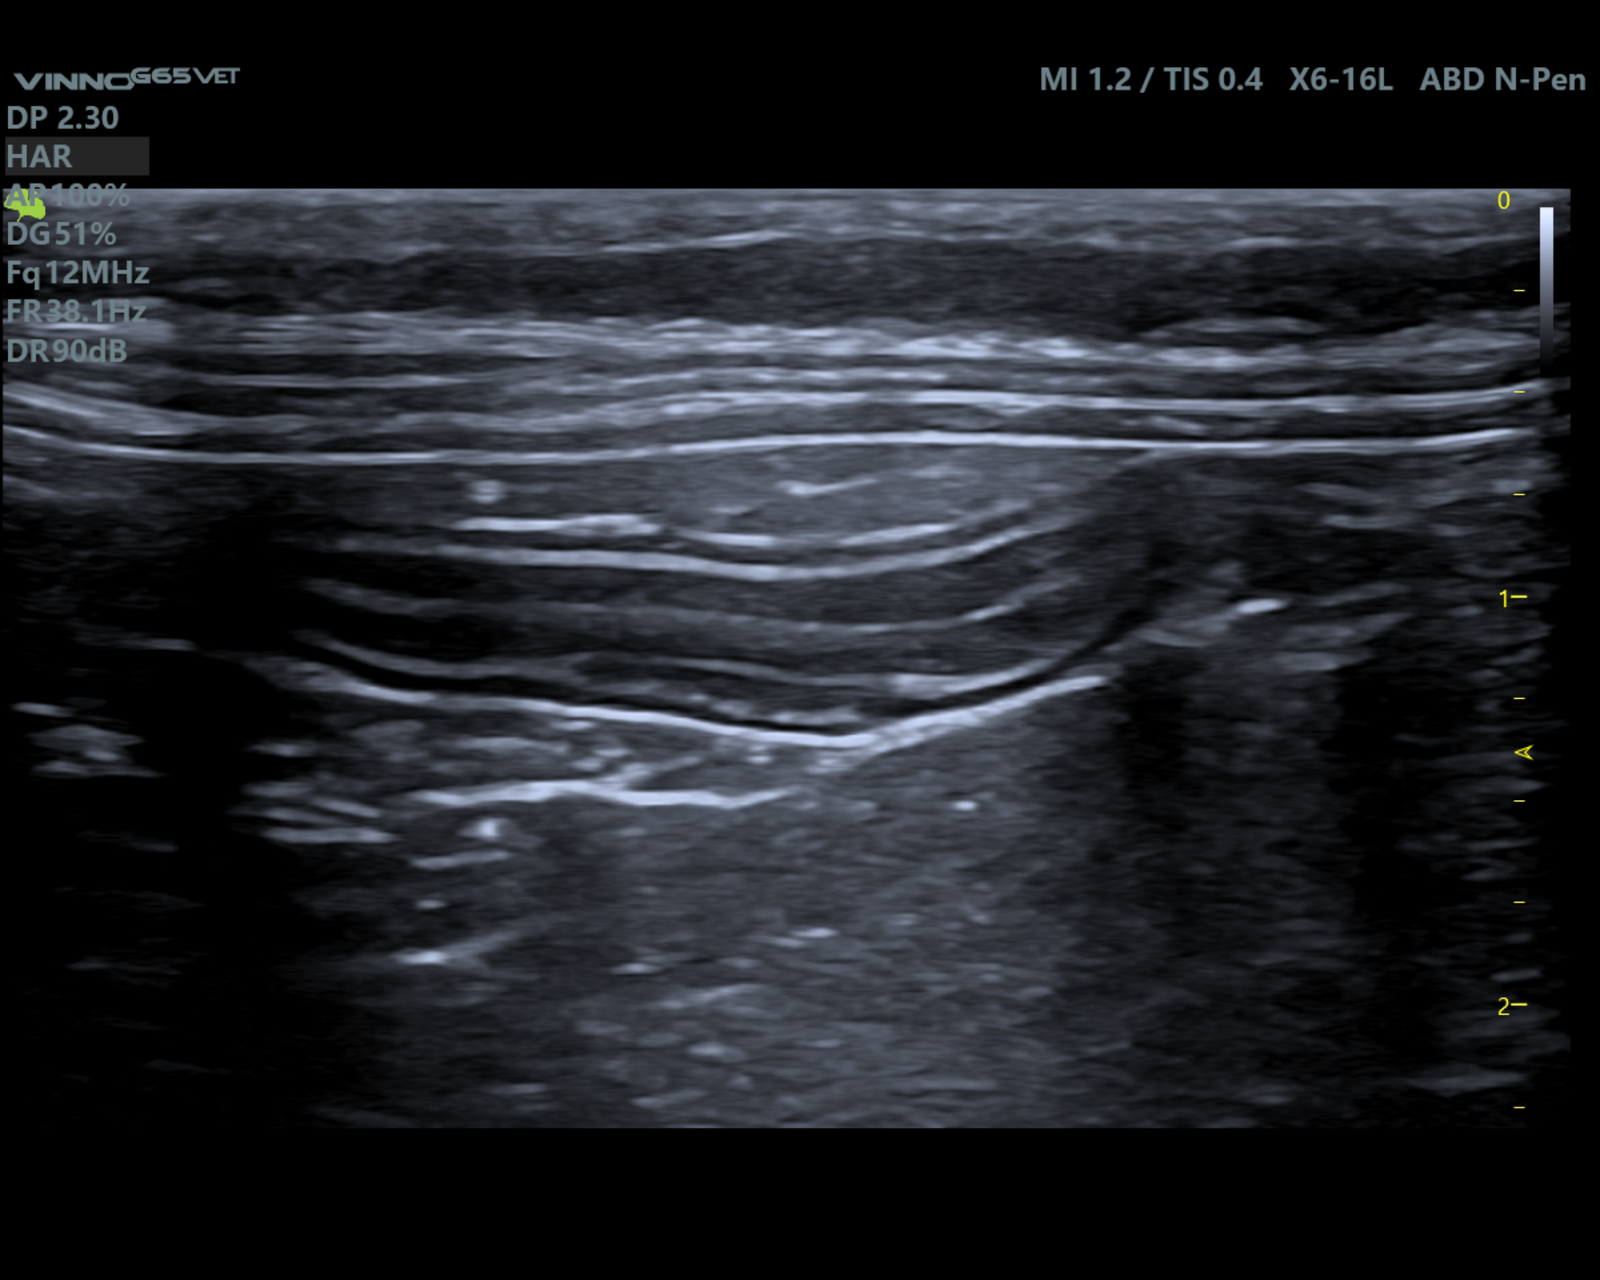

Badanie USG przeprowadziła lek.wet. Monika Morawska z MOONVET Aparat: VINNO G65VET Pacjent: 9-letnia, kastrowana kotka, u której wcześniej wykonano amputację kończyny miednicznej z powodu rozrostu w okolicy stawu skokowego. Histopatologia guza wskazała na mięsaka —złośliwy nowotwór pochodzenia mezenchymalnego. Podczas badania stwierdzono powiększenie prawego węzła chłonnego biodrowego pośrodkowego oraz węzła pachwinowego. Pobrany materiał z węzła biodrowego […]